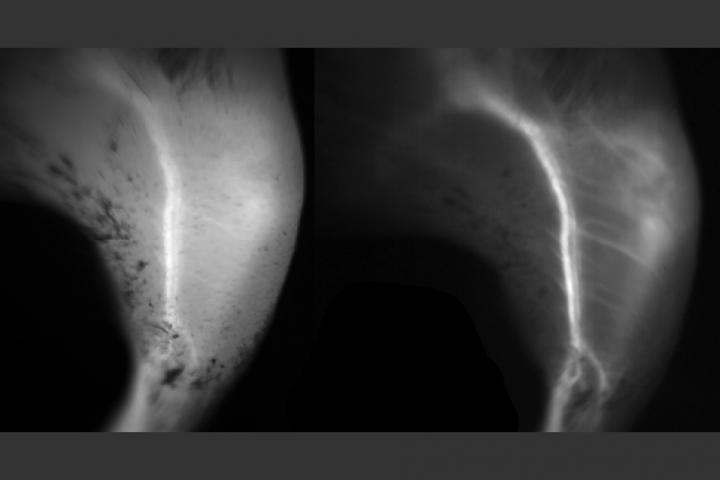

Fluorescence imaging is widely used for visualizing biological tissues such as the back of the eye, where signs of macular degeneration can be detected. It is also commonly used to image blood vessels during reconstructive surgery, allowing surgeons to make sure the vessels are properly connected.

For these procedures, as well as others now in clinical trials, such as imaging tumors, researchers use a portion of the light spectrum known as the near-infrared (NIR) -- 700 to 900 nanometers, just beyond what the human eye can detect. A dye that fluoresces at this wavelength is administered to the body or tissue and then imaged using a specialized camera. Researchers have shown that light with wavelengths greater than 1,000 nanometers, known as short-wave infrared (SWIR), offers much clearer images than NIR, but there are no FDA-approved fluorescence dyes with peak emission in the SWIR range.

"In the near-infrared, a lot of the features you see in tissue can look foggy, and once you move into the short-wave infrared, the image clears up and everything becomes sharp," Bruns says.

"We found that short-wave infrared is particularly useful for imaging small objects that are on top of a large background, so when you want to do angiography of small vessels, or capillaries, that's significantly easier in the short-wave infrared than in the near-infrared," Franke says.